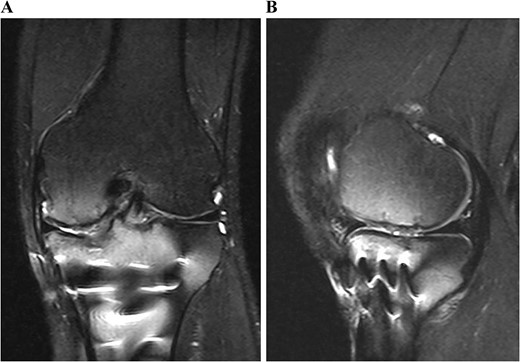

Postoperative MRI at 1 year after the surgery showed that the transplanted cultured cartilage had successfully integrated without any delamination (Fig. 6). A second-look arthroscopy was performed to evaluate the condition of the transplanted cartilage while removing the plate. The cartilage defect of the medial femoral condyle was covered by hyaline cartilage-like tissue. The depressed articular surface of the medial tibia plateau was smooth without stepping off (Fig. 7). One year after the surgery, the patient resumed daily life and sports activities without any complaint. The patient’s range of motion of the knee was full, and Lysholm’s knee score was 95.

Postoperative T2-weighted fat-suppressed magnetic resonance images at 1 year after surgery. The transplanted cultured cartilage was successfully integrated without any delamination.